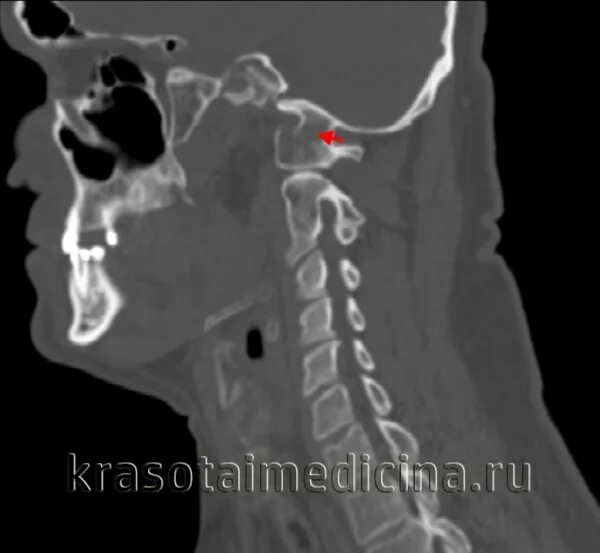

Атлант кт